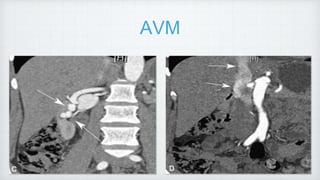

AVM

abnormal communications between the intra- renal arterial and venous vessels.

Types : i) Congenital [1/3rd] ii) Acquired [2/3rd]. -

iatrogenic

Cirsoid [MC] Cavernous AVM

Dilated corkscrew app Single dilated vessel

aka renal AV fistulas

US -Turbulent flow within renal parenchyma

• #44 diagnosis can be made by detection of high-velocity flow within the feeding artery and pulsatile flow within the affected vein. Renal arteriovenous malformation (AVM). A, Gray-scale image of the right kidney reveals multiple ser- pentine anechoic tubular structures (arrows). B, Color Doppler image of the right kidney demonstrates color aliasing in the dilated feeding artery and draining vein of the AVM (arrow).

• #45 C, Computed tomographic (CT) angiography in this patient reveals multiple dilated enhancing vessels in the right renal cortex (arrows). D, CT angiography reveals early fill-in of the suprarenal inferior vena cava (arrows).